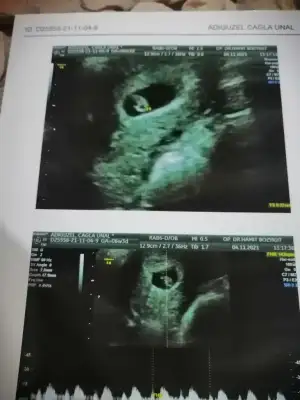

Canım kaçıncı haftadasn senManyakPrenses canım merhaba ultrason cinsiyet için tahminin ne bakarmısın benim için birde kalp atışı dk 143 çıktı çok şükür kalp atışı gördük

6+6 haftalık gözüktü bugün aslında 6+3 bebek önden gidiyormuşCanım kaçıncı haftadasn sen

Canım kese fasulye gibi erkeğe benzettim benManyakPrenses canım merhaba ultrason cinsiyet için tahminin ne bakarmısın benim için birde kalp atışı dk 143 çıktı çok şükür kalp atışı gördük